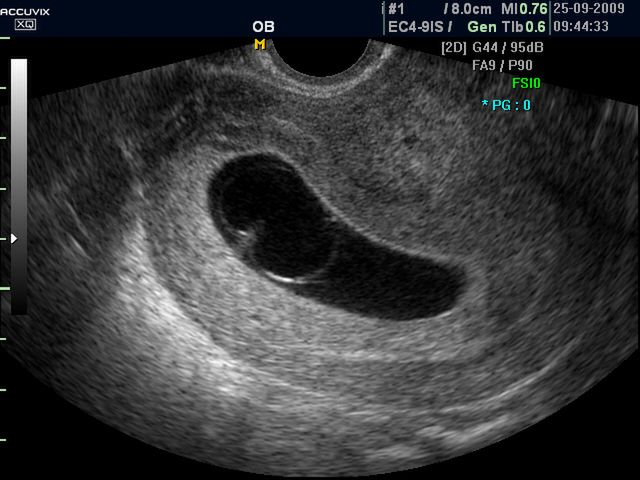

Płód w 9 tygodniu ciąży (bliźniaki jednokosmówkowe) -zdjęcia

W 9 tygodniu kształtują się nos, usta, powieki. Zanika charakterystyczny dla embriona ogonek